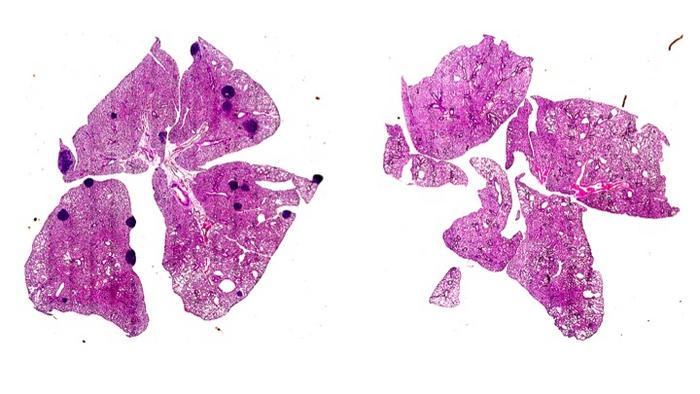

Utilizing a mouse model of melanoma, the researchers demonstrated that aspirin administration led to a marked reduction in the frequency of metastases, affirming their hypothesis that the drug facilitates T cell reactivation against cancer cells by alleviating the suppression previously imposed by TXA2. This synergistic effect highlights the potential of aspirin not just as an analgesic, but as a powerful immunomodulatory agent capable of modifying the landscape of metastatic cancer.